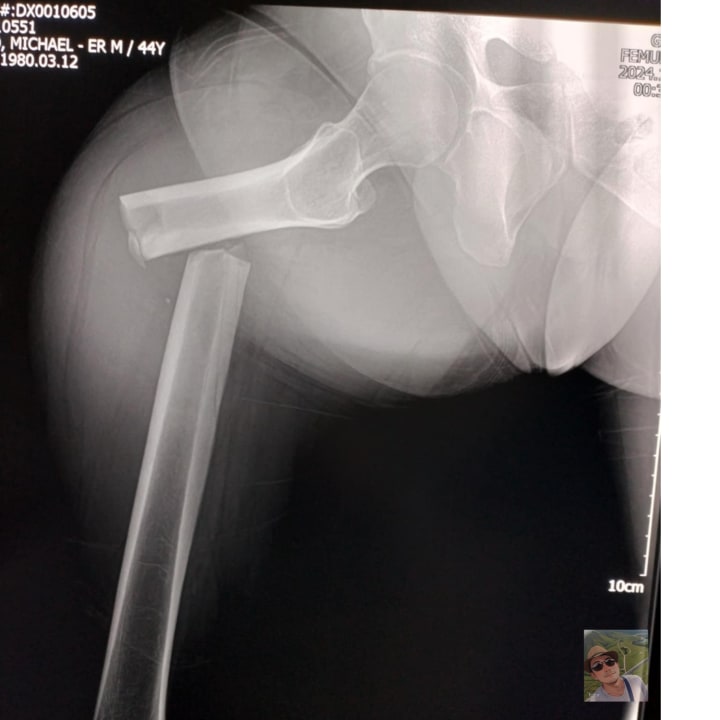

Have you ever faced a daunting moment when it felt like your world had reached a standstill? For me, that moment arrived unexpectedly one sunny afternoon when I fractured my right femur. The vibrant rhythm of my daily life was instantly replaced by the slow, arduous steps of rehabilitation. It was a challenging path, but amidst the pain and frustration, I discovered a newfound source of strength and inspiration — music.

It was a typical day, filled with the usual hustle and bustle. Little did I know, a simple misstep would turn my life upside down. One moment I was walking down the lane in front of my house, and the next, I found myself lying on the pavement, my leg broken and my world seemingly shattered. The diagnosis was clear: a fractured femur meant months of recovery, physical therapy, and a significant lifestyle adjustment.